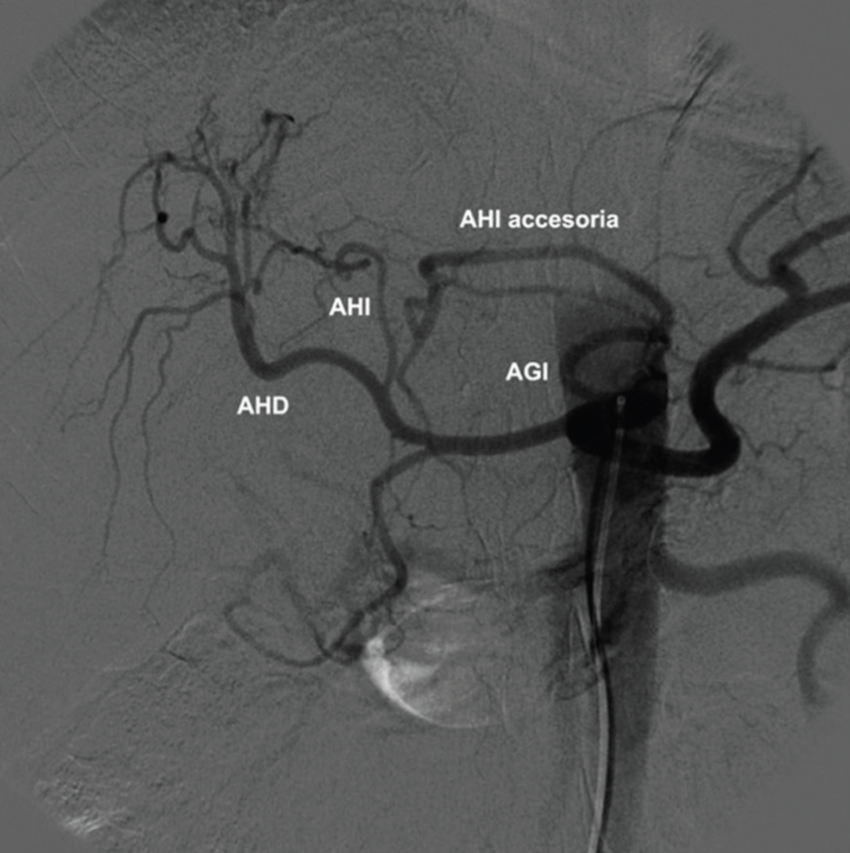

Tipo 5: AHD y AHI con origen en la AHC. AHI accesoria desde la AGI (Fig. 10).

Tipo 6: AHD y AHI con origen en la AHC. AHD accesoria desde la AMS (Figs. 11 y 12).

Tipo 7: AHD y AHI con origen en la AHC. AHD accesoria desde la AMS y AHI accesoria desde la AGI (Figs. 13 y 14).